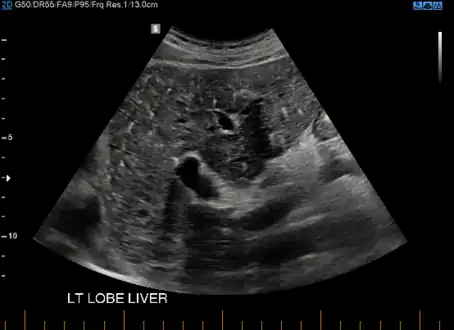

- von Meyenburg Complex in ultrasound. Numerous little cysts with ringdown artefacts.